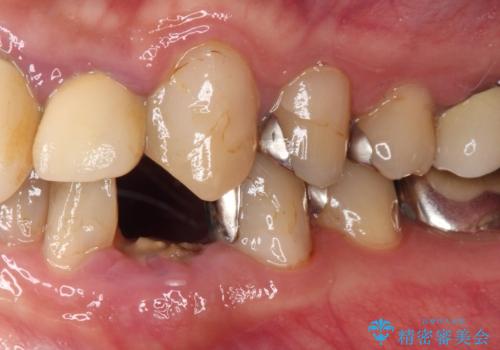

当該歯である犬歯は歯根が長く、安易に抜歯することはおすすめできないため、まずは部分矯正により歯根を引っ張り出し、その後歯周外科処置により歯槽骨や歯肉の状態を整え、最終的にはオールセラミッククラウンにて補綴治療を行うこととしました。

矯正治療中は汚れが溜まりやすく、歯肉からの出血が続きましたが、最終的には歯を保存して安定した状態で補綴治療を行うことができました。